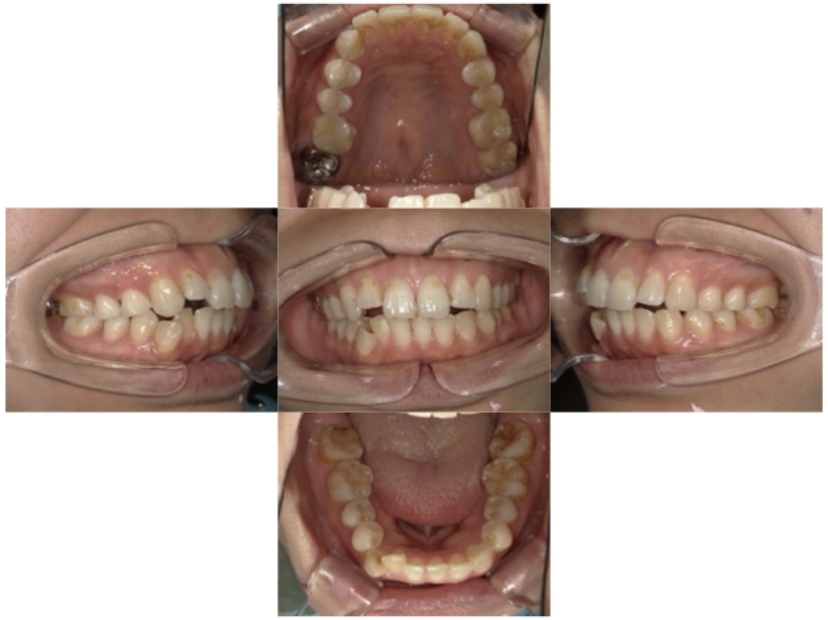

症例2

上下顎前突、叢生

抜歯

ブラケット矯正

上下顎前突、叢生(上下出っ歯、上下の前歯のガタガタ)のケースです。

装置はラビアル(上下表側)で、上下顎の小臼歯を4本抜歯を行っています。抜歯したスペースを使って、上下の前歯の後方移動と叢生(ガタガタ)の改善を行っています。

主訴 前歯のガタガタと口元がでているのが気になる。

年齢・性別 30歳 女性

お住まいの地域 東京都大田区

治療方針 抜歯スペースを利用して上前歯の叢生(ガタガタ)と口元突出の改善

抜歯部位 上下顎左右第一小臼歯

使用装置 ラビアル(上下表側)、顎間ゴム

治療期間 1年11か月

治療回数 13回

リテーナー クリアリテーナー

BEFORE

AFTER